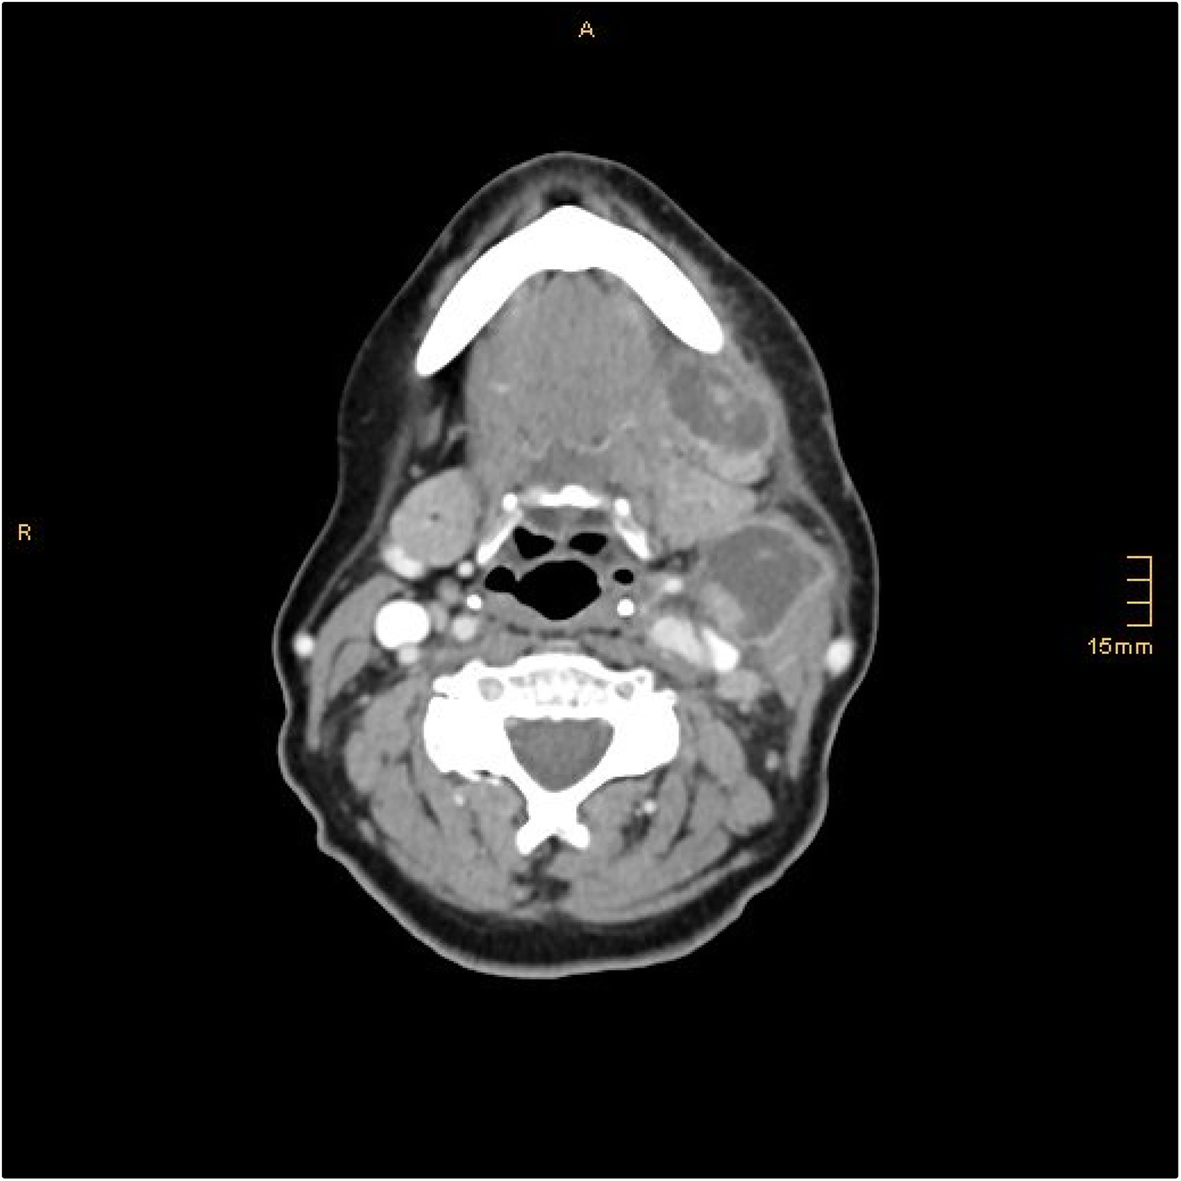

From www.researchgate.net

(PDF) Lymph node abscess caused by Francisella tularensis a rare Abscess Tooth Lymph Node Pain when chewing or biting. Such infections can occur due to tooth decay, gum disease, or a. The lymph nodes act as filters for the fluids, and the lymphocytes produced within the lymph nodes combat infections that might. An abscess is the medical term for a pocket of pus and bacteria that. Symptoms that a tooth infection has spread to. Abscess Tooth Lymph Node.

From link.springer.com

Lymph node abscess caused by Francisella tularensis a rare Abscess Tooth Lymph Node Tender or swollen lymph nodes in the neck or jaw area can also be a sign of a tooth abscess. A dental abscess can travel to the brain. Sometimes, these bacteria can enter into a tooth or below the gumline, resulting in a tooth infection or abscess. Sensitivity to heat and cold. Periapical abscess symptoms may include: Teeth sensitivity to. Abscess Tooth Lymph Node.